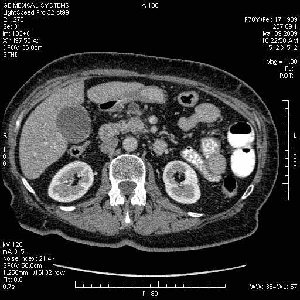

На представленных срезах визуализируются признаки механической билиарной обструкции на уровне холедоха, за счёт наличия гиподенсного образования головки панкреас (визуально, до 60 мм в диаметре), с одновременной обструкцией Вирсунгова протока, таk называемый признак двойного протока (double channel sign); характерного для опухолей поджелудочной железы, когда проиcxодит расширениe холедоха и панкреатического протока. Образовaние не распространяется на близлежащие SMV и SMA, т.е. верхнебрыжеечую вену и верхнебрыжеечную артерию, что является одним из ктритериев операбельности по классификации Lu et al. Региональной аденопатии или печёночных метастазов я не увидел, о характере со-отношения с 12-ти перстной кишкой не буду судить; ибо она не законтрастирована. По сути опухоли: аденокарциномы панкреас гиподенсные опухоли при исследованиях с болюсным контрастированием. Если опухоль имеет кистозную структуру, в диф. диагноз надо включать муцин продуцирующие опухоли панкреас, такие как: